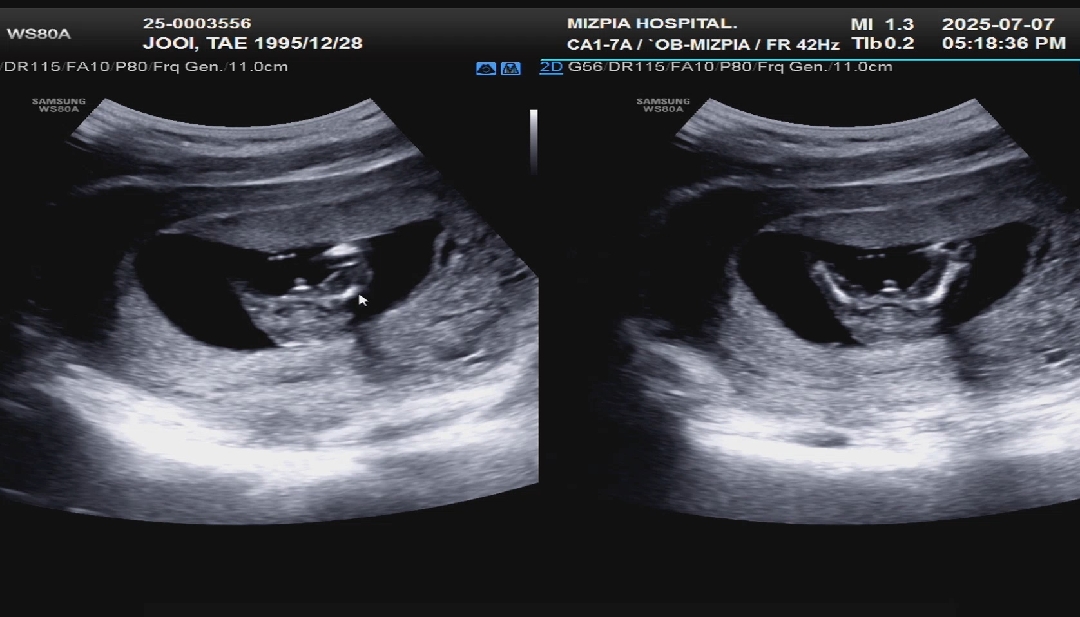

14주 0일 성별반전 없을까요ᆢ?

오늘 너무 머리아프고 해서 촘파보러갔다가 아가가 다리를 좌악 벌리고있어서 얼결에 가랭이 직관했는데 왜 뭐가 있죠ᆢ? 매끈해야되는데ᆢ? ㅠㅠㅠ 반전 없을까요ㅜㅜㅜㅜㅜ

저 첫째 14주에 명확히 고추가있고 선생님도 고추가 있네요^^ 하셨는데, 16주에 고추 떼지고 지금 3살 여자아기 키우고있어요ㅎㅎ 다음 촘파까지 기다려보셔요! 아직 정확하디않습니당

다음 진료가 15주 4일차인데 그때도 고추있으면 포기해야되겠죠ᆢ? ㅠㅠ